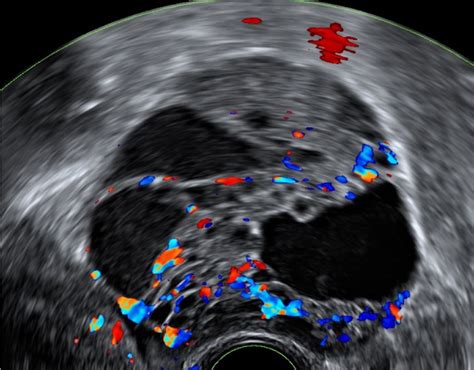

Število foliklov je neposredno povezano z jajčno rezervo ženske, ki predstavlja količino jajčec, ki so na voljo za oploditev. Z naraščajočo starostjo se število foliklov zmanjšuje, kar naravno vpliva na možnost zanositve. Eden najpomembnejših kazalnikov plodnosti je antralni folikel - folikel v zgodnji fazi razvoja, ki je viden na ultrazvoku. Kot navaja Cleveland Clinic, antralni folikli pomagajo napovedati odziv jajčnikov na hormonsko stimulacijo med postopki oploditve z biomedicinsko pomočjo (IVF). Merjenje števila antralnih foliklov (AFC) preko transvaginalnega ultrazvoka, običajno med 2. in 5. dnem menstrualnega cikla, je eden od ključnih testov plodnosti. Vrednosti AFC se običajno kategorizirajo kot:

Preveliko število foliklov, zlasti tistih, ki ne dozorijo pravilno, je pogosto povezano s sindromom policističnih jajčnikov (PCOS). Pri PCOS folikli ne dozorijo, kar vodi v neredne cikle in težave z ovulacijo. Na ultrazvoku se PCOS diagnosticira, ko je v posameznem jajčniku več kot 12 foliklov premera 2-9 mm in/ali je povečana prostornina jajčnika nad 10 ml. Ti jajčniki imajo pogosto zadebeljeno steno in spremenjeno strukturo folikularne ovojnice. Poleg tega PCOS vključuje tudi hormonske motnje, ki dodatno otežujejo zanositev.